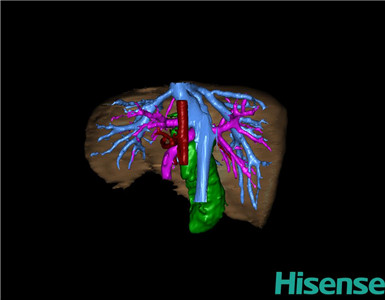

将0.625mm双源薄层CT资料的静脉期和动脉期Dicom格式文件导入海信CAS系统。

通过调节窗宽窗位调整CT序号,对肝实质,胆囊,胆总管,下腔静脉,肝动脉、门静脉及肝静脉等进行三维重建;系统自动计算肝脏体积。

术前手术方案的规划。

术前三维重建:

重建图片